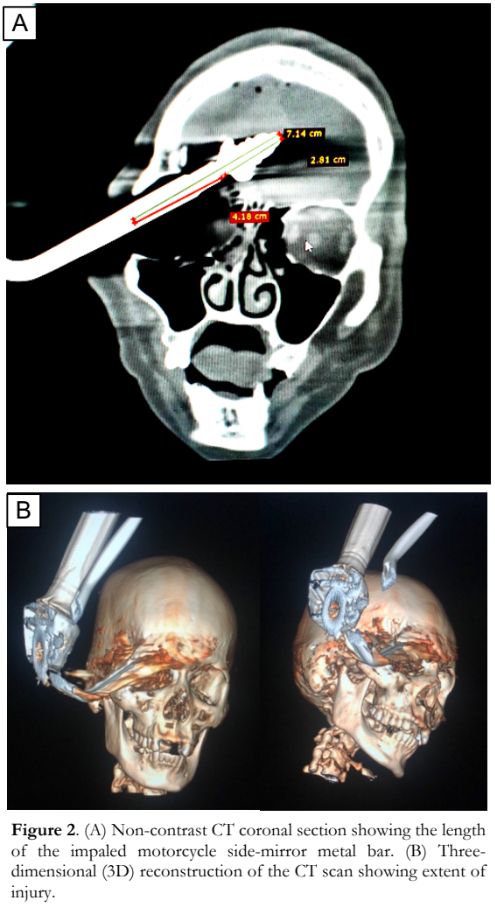

Plain computed tomography (CT) scan demonstrated the motorcycle side-mirror metal bar traversing the right orbit and extending into the right frontal lobe substance with its tip within the anterior cranial fossa (Figure 2). The penetrating segment of the metal spanned 7.14 centimeters (cm), while its distal 2.81 cm exhibited a distinctive bulbous threaded configuration, puncturing the right frontal lobe. There was an ill-defined appearance of the right globe suggestive of rupture. Multiple fractures were seen in the posterior wall of the right frontal sinus and right lamina papyracea, and there were comminuted fractures involving the right orbital roof and floor. There were no other fractures or dislocation in the calvarium and basal skull structures. There were also hyperdense foci in the bilateral frontal lobe parenchyma, bilateral fronto-parietal cortical sulci as well as along the interhemispheric fissure consistent with contusion hemorrhages of bilateral frontal lobes and subdural hemorrhages in the interhemispheric fissures. Air pockets were seen along the bilateral frontal convexities and anterior interhemispheric fissure. There was no brain edema nor hemorrhage. The patient was started on intravenous broad-spectrum antibiotics for pre-operative prophylaxis.